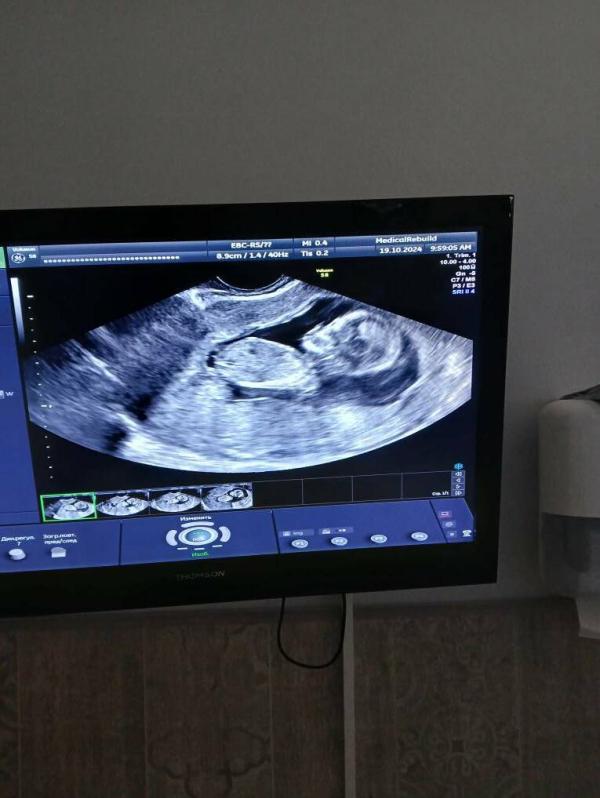

Наша малышка🥰 Привет сегодня передавала

@mariazem как правило такой анализ не ошибается,максимум могут перепутать) да и лучший узист в городе подтвердил девочку. Мальчики наши на 1м скрининге ножки раздвигали и уже показывали достоинство 😅